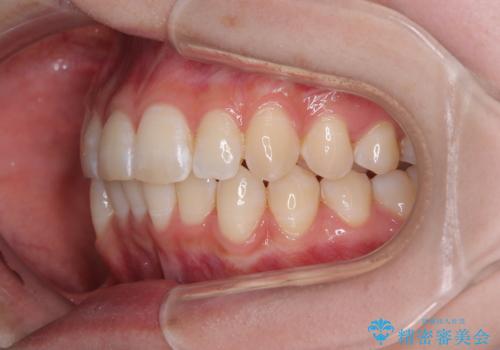

- 上下前歯の重なりを気にして来院された患者様です。

安価なインビザラインパッケージを用いての治療を希望されており、デコボコの程度が中等度であったため、インビザライン・モデレートを用いて矯正治療を行うこととしました。

インビザライン・モデレートは、製作できるアライナーの枚数に制限があるため、移動可能な量に限りがあるものの、インビザライン・ライトよりも枚数が多いため、幅広い症例に対応可能です。